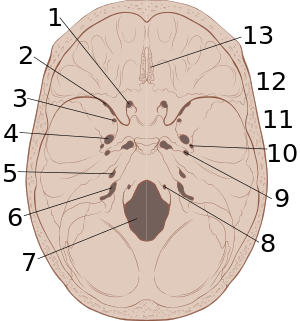

النزف فوق الجافية Epidural hematoma، هو نزف يحدث بين الجمجمة والجافية (الطبقة الخارجية من السحايا).

يحدث في الحالات الوصفية فقدان وعي عابر بعد الرضِّ الدماغي، ومن ثم يستعيد المريض وعيه وتجاوبه مدة عدة ساعات، وبعدها يعود الوعي إلى التدهور مع حدوث ضعف شقي مقابل واتساع في حدقة العين في الجانب الموافق للنزف. وجدير بالذكر أن هذه الأعراض التقليدية تحدث على هذا النحو في 10ـ 25% من الحالات فقط. ومن الأعراض الأخرى الصداع والإقياء والاختلاجات. قد تؤدي الحالة إلى الوفاة نتيجة انضغاط مراكز دماغية حساسة (كتلك المسؤولة عن التنفس) إن لم يعالج النزف.

يحدث هذا النوع من النزف في نحو 1% من المرضى الذين يدخلون المشفى بسبب رضّ دماغي، وينتج عادة من حدوث كسر في المنطقة الصدغية الجدارية من الجمجمة. مما يؤدي إلى تمزق الشريان السحائي المتوسط وحدوث النزف. وفي قلة من الحالات يكون منشأ النزف من الأوردة (وليس الشرايين) السحائية.[1]

قد تبدي الصورة البسيطة للجمجمة وجود كسر. لكن الاختبار الأمثل للتشخيص هو التصوير الطبقي المحوري للدماغ CT.scan، فهو يُظهر النزف على شكل منطقة عالية الكثافة محدبة من الجهتين ومحاذية للجمجمة.